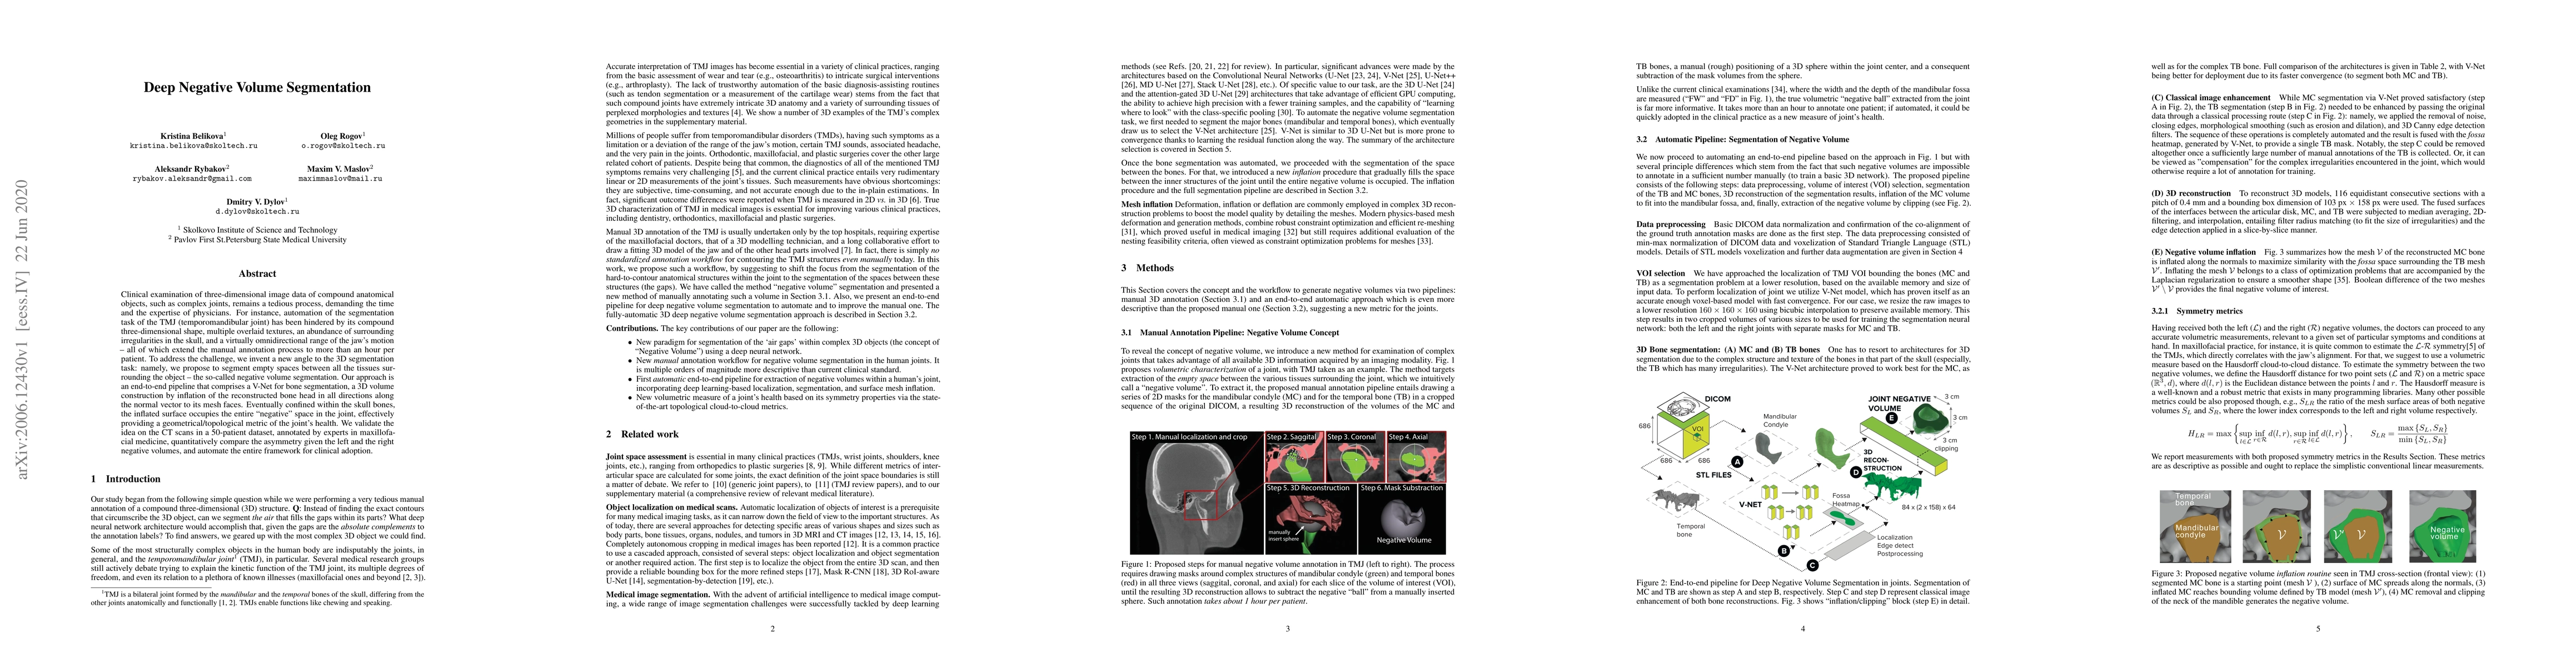

Clinical examination of three-dimensional image data of compound anatomical objects, such as complex joints, remains a tedious process, demanding the time and the expertise of physicians. For instance, automation of the segmentation task of the TMJ (temporomandibular joint) has been hindered by its compound three-dimensional shape, multiple overlaid textures, an abundance of surrounding irregularities in the skull, and a virtually omnidirectional range of the jaw's motion - all of which extend the manual annotation process to more than an hour per patient. To address the challenge, we invent a new angle to the 3D segmentation task: namely, we propose to segment empty spaces between all the tissues surrounding the object - the so-called negative volume segmentation. Our approach is an end-to-end pipeline that comprises a V-Net for bone segmentation, a 3D volume construction by inflation of the reconstructed bone head in all directions along the normal vector to its mesh faces. Eventually confined within the skull bones, the inflated surface occupies the entire "negative" space in the joint, effectively providing a geometrical/topological metric of the joint's health. We validate the idea on the CT scans in a 50-patient dataset, annotated by experts in maxillofacial medicine, quantitatively compare the asymmetry given the left and the right negative volumes, and automate the entire framework for clinical adoption.